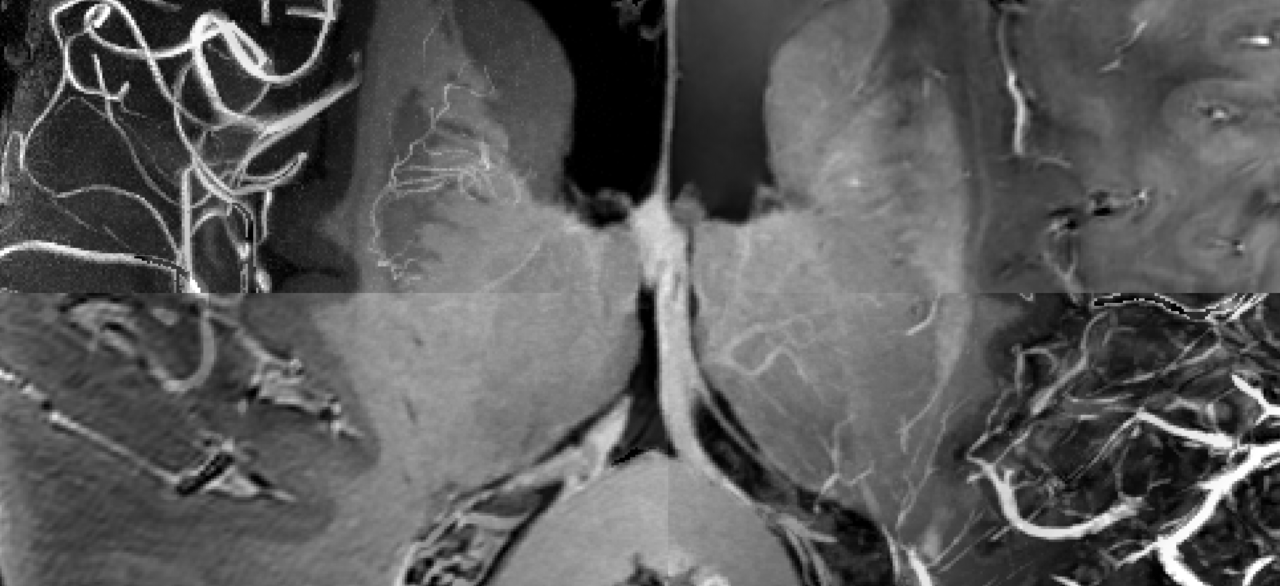

Today, we are happy to share a decade worth of MRI data of a single participant as a human phantom in our recent data descriptor published in Scientific Data available here: https://rdcu.be/clgFK. We present an extension to our previous dataset containing multiple additional contrasts with ultrahigh isotropic spatial resolution and (mostly) full brain coverage. In total, 202 volumes were acquired across 66 scanning sessions using an ultrahigh field 7 Tesla MR scanner (Siemens Heathineers, Erlangen, Germany). This includes up to 150 μm time of flight (ToF) angiography, 250 μm MPRAGE, 330 μm quantitative susceptibility mapping (QSM), up to 450 μm T2-weighted turbo spin echo (TSE), eight 700 μm T1-weighted back-to-back scans with low and high signal to noise ratio (SNR), 800 μm diffusion tensor imaging (DTI), one hour continuous 1.8 mm resting-state functional MRI (rs-fMRI), and more than 120 other MPRAGE volumes collected over 10 years with varying isotropic spatial resolution between 450 μm and 1 mm as well as many corresponding proton density weighted volumes with the same spatial resolution as the MPRAGE volumes.

Therefore, we expect this new dataset to be used in many multimodal processing schemes, e.g. data fusion for visualization as well as teaching, building of brain atlases, vascularization of subcortical structures such as the hippocampus, validation of connectivity models based on joint DTI and rs-fMRI data and many things beyond. Due to its ultrahigh resolution and high quality, we expect to see structures that were never identified before in vivo. Further, structural and vascular differences in the laminar organization of the cortex could be investigated by assessing jointly the MPRAGE (cortical delineation), QSM (iron, myelin proxy; venous vasculature), ToF (arterial vasculature), and DTI (intra-cortical fiber tracts). The MPRAGE volumes have been collected over ten years and can be used in different kinds of studies. First and foremost, they can be used to conduct longitudinal studies. This could for example indicate longitudinal changes across time. However, since the scanning protocol is not identical for every measurement, this could be an ideal test bed for novel data harmonization algorithms to avoid potential bias in data assessment. Furthermore, data is included in back to back studies within the very same session and with artificially reduced SNR. This may allow for test-retest studies in software development and to validate denoising algorithms as ground truth data can be generated. Beyond that, the scanner's rawdata of the back to back scans are available which allow for development and benchmarking of advanced reconstruction algorithms.